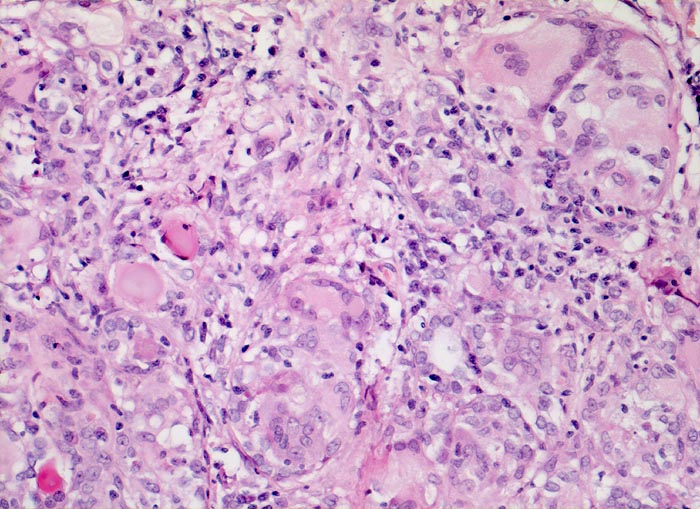

AP/ Subakute Thyeroiditis de Quervain

Subakute Thyeroiditis de Quervain

Schilddrüse

Pathologischer Befund